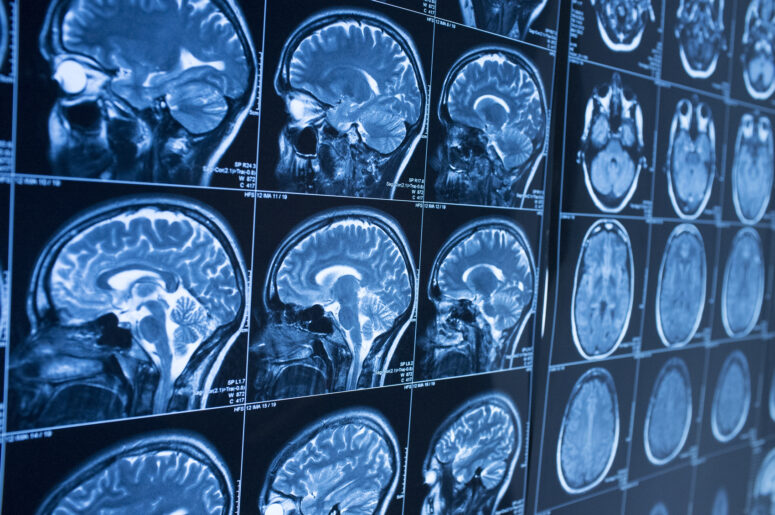

Most people do not realize it, but serious brain injuries can be a result of automobile collisions even when the impact is fairly low-speed. Occasionally, they can even happen when passengers are otherwise uninjured if other factors like whiplash are at play. This is because traumatic brain injuries, or TBIs, can stem from a variety of causes, including severe concussion. They can also seriously impair one’s ability to function professionally and personally, leading to lost income and serious health consequences.

To really understand what these facts mean, you have to understand how they fit together. When an accident victim has experienced a TBI, the injury is on the brain itself, and often there is some internal bruising or bleeding. Typically, those who live through the first few days after a TBI survive, but the amount of impairment and the type are often unknown for some time. Symptoms tend to present themselves over time, and it can take years for a patient’s recovery to plateau into a state that represents a new normal.

Traumatic brain injury can be difficult to understand and even more difficult to properly treat because the symptoms develop and change so much as the brain heals that the effects can be hard to predict. To take care of your medical needs and lost wages, you need to talk to an attorney with the experience to navigate the claim and settlement process.